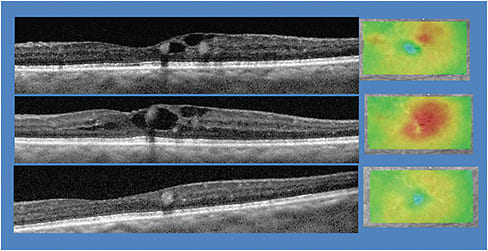

- SD-OCT. This technology acquires scans of the macula and choroid, providing an unprecedented view of the macular anatomy, enabling subtle cases of DME to be detected earlier. There is consensus that the central retinal thickness measured with SD-OCT is the reference standard for the assessment of DME.5